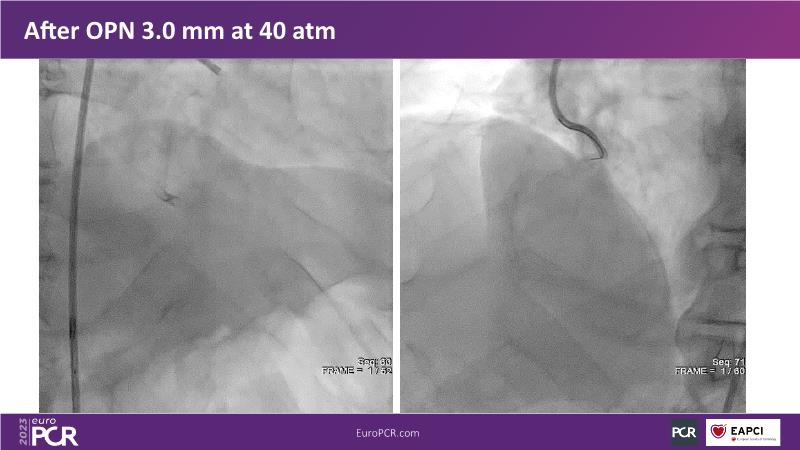

In this session, review the evolution in the use of IVL over the last few years, with a widening of the indications, observe that OCT can underestimate the number and depth of calcium fractured induced by IVL, or see that the technique is safe and effective in high-risk patients, including ACS patients, as demonstrated in real-world registries, among others!

- To understand how intravascular lithotripsy (IVL) in clinical practice has evolved over the last five years

- To evaluate the effects of IVL in different patterns of calcific coronary disease